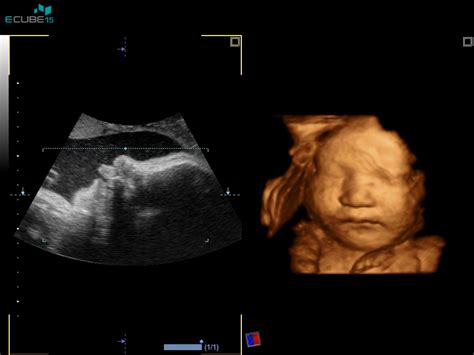

Sodobna 3D/4D ultrazvočna tehnologija omogoča zelo realističen prikaz razvijajočega se ploda. Pregled se lahko opravi že v prvem trimesečju ob pregledu nuhalne svetline. Možen je ob morfološkem pregledu ploda v drugem tromesečju. Najobičajnejši je 3D/4D ultrazvočni pregled v tretjem tromesečju, ko je videz ploda že zelo dokončen in tak, kakršen bo videti plod ob rojstvu.